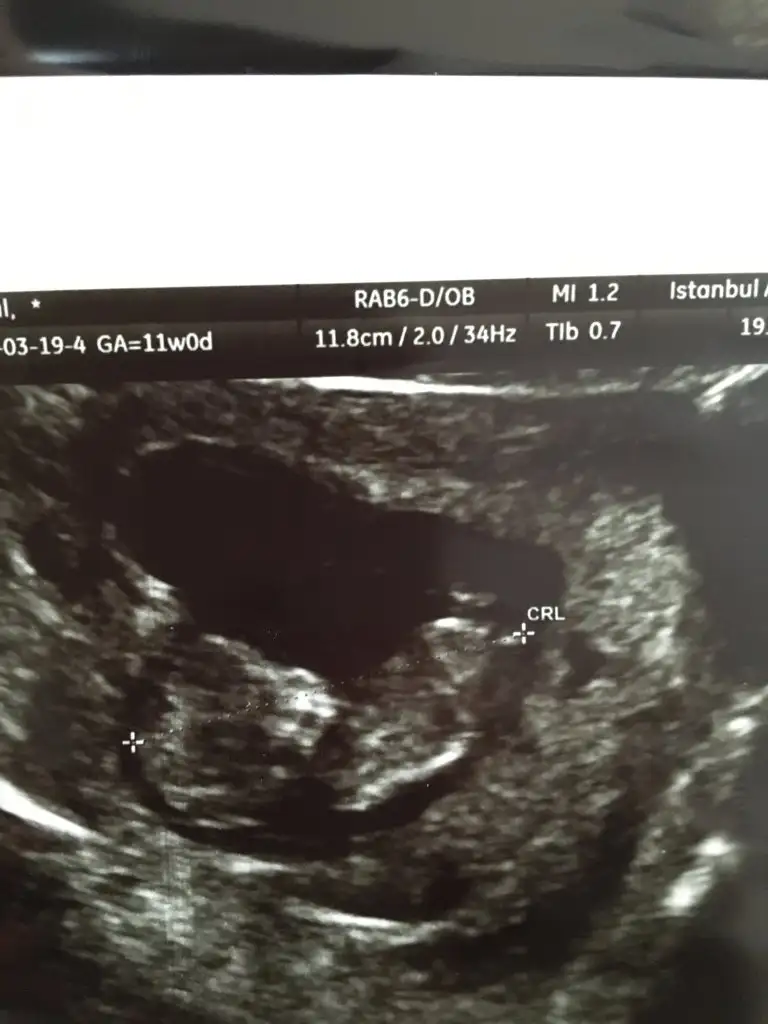

Eee sen balayını ilk üç ay yaptın şekerim sıra bizde.Burası balayı değil bildiriyorum bulantilar başladı![]()